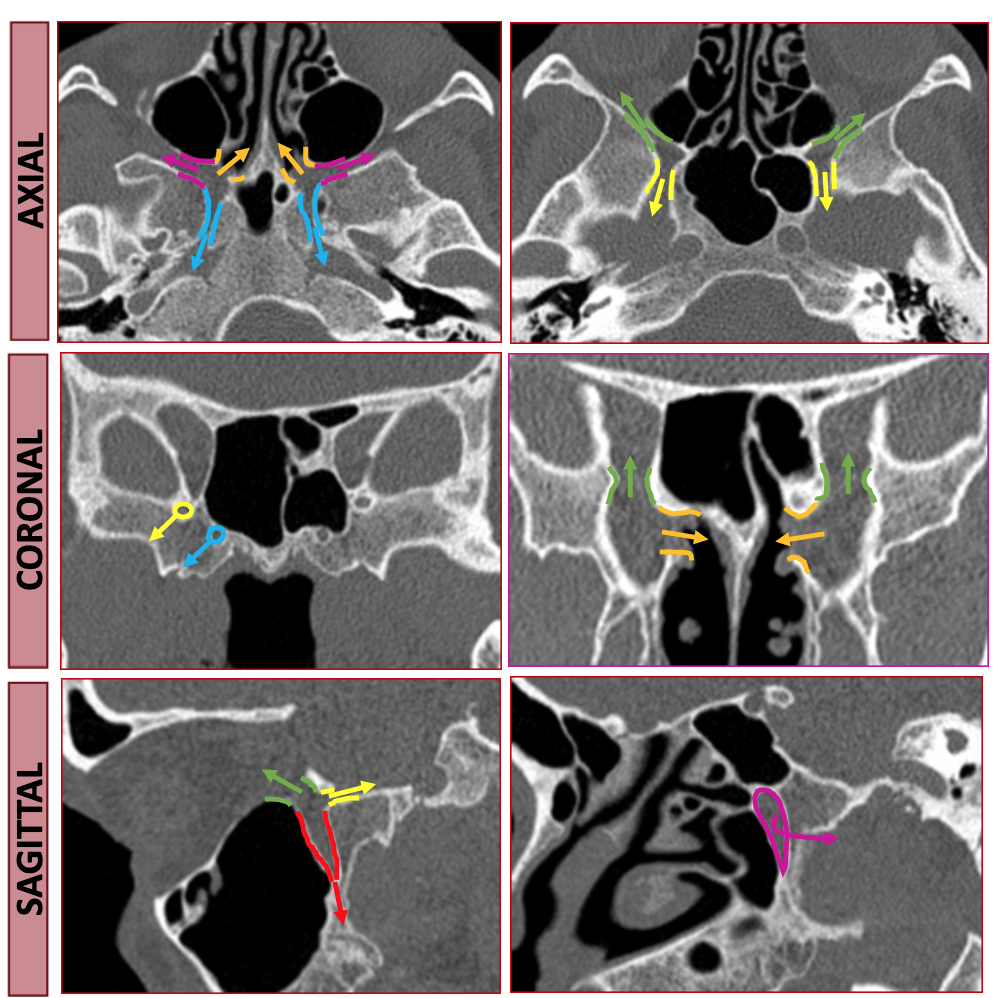

Pterygopalatine Fossa

• Should think of pterygopalatine fossa as one of the major intersections of the face/skull

The following pictures are a fantastic way to visualize the borders rather than just memorizing them which is a sure fire way to forget them by tomorrow.

• Anterior & Superior - communicates with inferior orbital fissure

• Inferior - Greater & lesser palatine canals

• Communicates with palate

• Lateral - Pterygomaxillary fissure

• Communicates with masticator space

• Medial communication - Sphenopalatine foramen & Palatine bone

• Communicates with nasal cavity

• Transmits

• Sphenopalatine artery

• Posterior superior nasal nerves & nasopalatine nerve

• Posterior

• Posterior-medial - Palatovaginal canal

• Communicates with nasopharynx

• Transmits pharyngeal nerve and pharyngeal branch of maxillary artery

• Posterior-superior - Foramen rotundum

• communicates with Meckel cave & Cavernous sinus

• Posterior-inferior - pterygoid canal (aka vidian canal)

• Communicates with middle cranial fossa

• Transmits vidian nerve, artery and vein

• Important space because allows spread of malignany